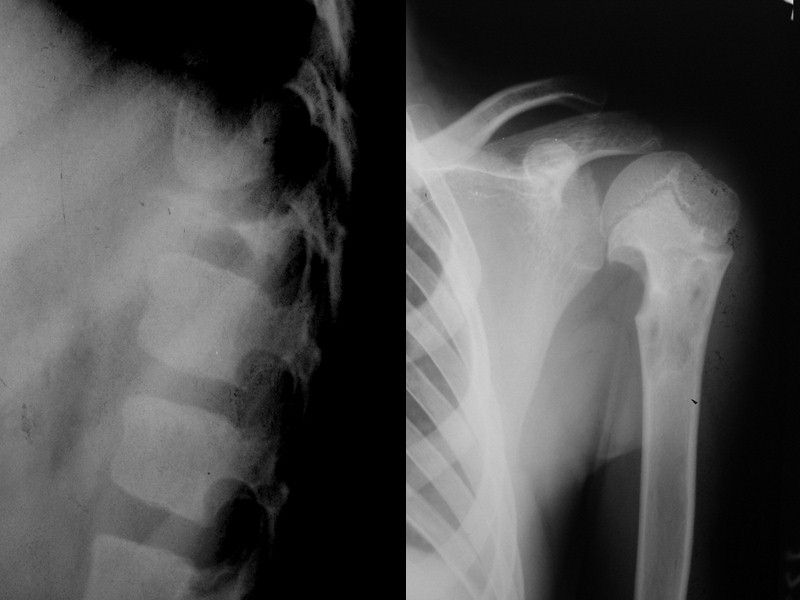

Хондробластома (опухоль Кодмана) До 2% от всех доброкачественных костных опухолей Выявляется в возрасте от 10 до 25 лет, в 2 раза чаще у мужчин Одиночная Преимущественная локализация – эпиметафиз длинных трубчатых костей Излюбленная локализация проксимальный эпиметафиз плечевой кости (опухоль Кодмена), не встречается в черепе является типом опухоли, переходным от хрящевой к остеогенной Может вызывать легкое вздутие кортикального слоя Не малигнизируется

Рентгенологические симптомы Выглядит как эксцентрично расположенный очаг просветления (хрящевая ткань), с вкраплениями костного вещества, с четким склеротическим контуром. Иногда прослеживаются линейные периостальные наслоения, которые быстро ассимилируются.